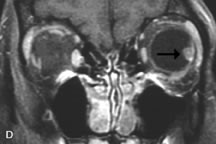

INTRAOCULAR TUMORS

On MRI, uveal melanomas have a typical appearance that helps to differentiate them from other primary and secondary intraocular tumors as well as choroidal detachments. Pigmented melanomas are hyperintense on Tl-weighted images, hypointense on T2-weighted studies, and hyperintense on proton density–weighted examinations (Fig. 24).30,31,50,80–82 These signal characteristics have been attributed to the paramagnetic properties of melanin because of stable free radicals that shorten the T1 and T2 relaxation times. Moderate enhancement is seen on postgadolinium T2-weighted images. Gadolinium-enhanced T1-weighted images are particularly sensitive in detecting choroidal melanomas.83 MRI may be less sensitive in detecting extrascleral extension of tumor than echography performed by an experienced ultrasonographer.84

Fig. 24. A. T1- and (B) T2-weighted MR scans demonstrate a small nodular intraocular mass (arrows) that is very hyperintense on the T1-weighted scan and hypointense on the T2-weighted image. This signal intensity pattern is due to the presence of free radicals within melanin granules. C and D. Postcontrast fat-suppressed T1-weighted scans demonstrate homogeneous intense enhancement of the lesion and no evidence of seleral penetration or optic nerve invasion.